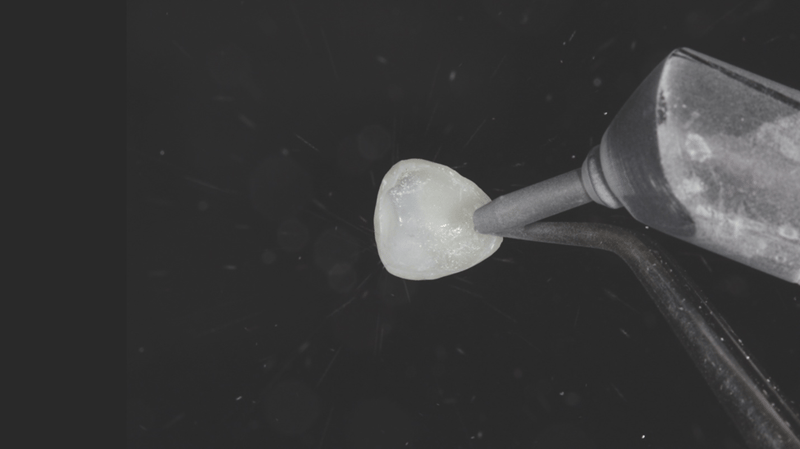

- Veneer-Separation: Vorsichtige und präzise Separation der Veneers mit Hilfe eines Skalpells (Nr. 12) und einem Separierstreifen.

- Entfernung der Kompositveneers

- Konturierung der Ränder: Konturierung der Ränder mit einem feinen Mosquito-Diamantbohrer zur gewünschten Form.

- Politur und Präparation für die Zementierung: Konturierung und Politur der Veneers mit dem Jiffy™ Natural Polierkit, in Vorbereitung auf die Zementierung.